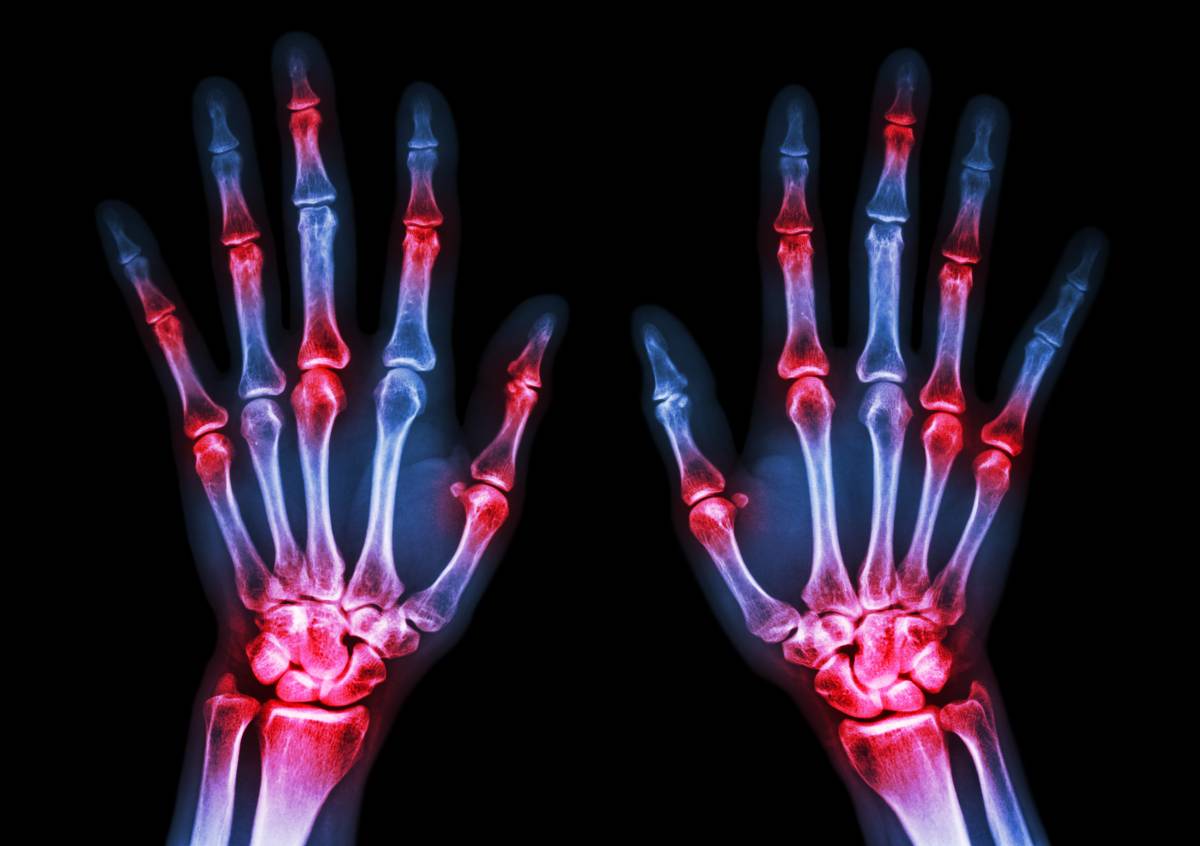

痛风的痛主要是尿酸盐结晶引起的。然而,尿酸钠要结晶沉积在某个地方并没有那么容易,需要具备几个条件:尿酸的量、周围的温度、体液酸碱度和体液的流动性等。温度和溶解度直接相关。同样体积的水,温水能比凉水溶解更多的盐或糖,尿酸盐也是一样的,容易在温度相对偏低的身体部位沉积。肢体的末端体温往往较低,如手、足、耳垂等部位温度偏低,是痛风石发生的常见部位。所以,痛风患者在冬季要做好保暖工作,外出戴手套、穿暖和的鞋子。